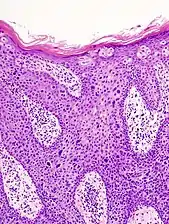

In invasive cSCC, tumor cells infiltrate through the basement membrane. The infiltrate can be somewhat difficult to detect in the early stages of invasion: however, additional indicators such as full thickness epidermal atypia and the involvement of hair follicles can be used to facilitate the diagnosis. Later stages of invasion are characterized by the formation of nests of atypical tumor cells in the dermis, often with a corresponding inflammatory infiltrate.[12]

Superficially invasive cutaneous squamous-cell carcinoma. These lesions often do not show the marked pleomorphism and atypical nuclei of cSCC in situ, but manifest early keratinocyte invasion of the dermis.[12]

Invasive nests with characteristic large celled centers. Ulceration (at left) is common in invasive cSCC.